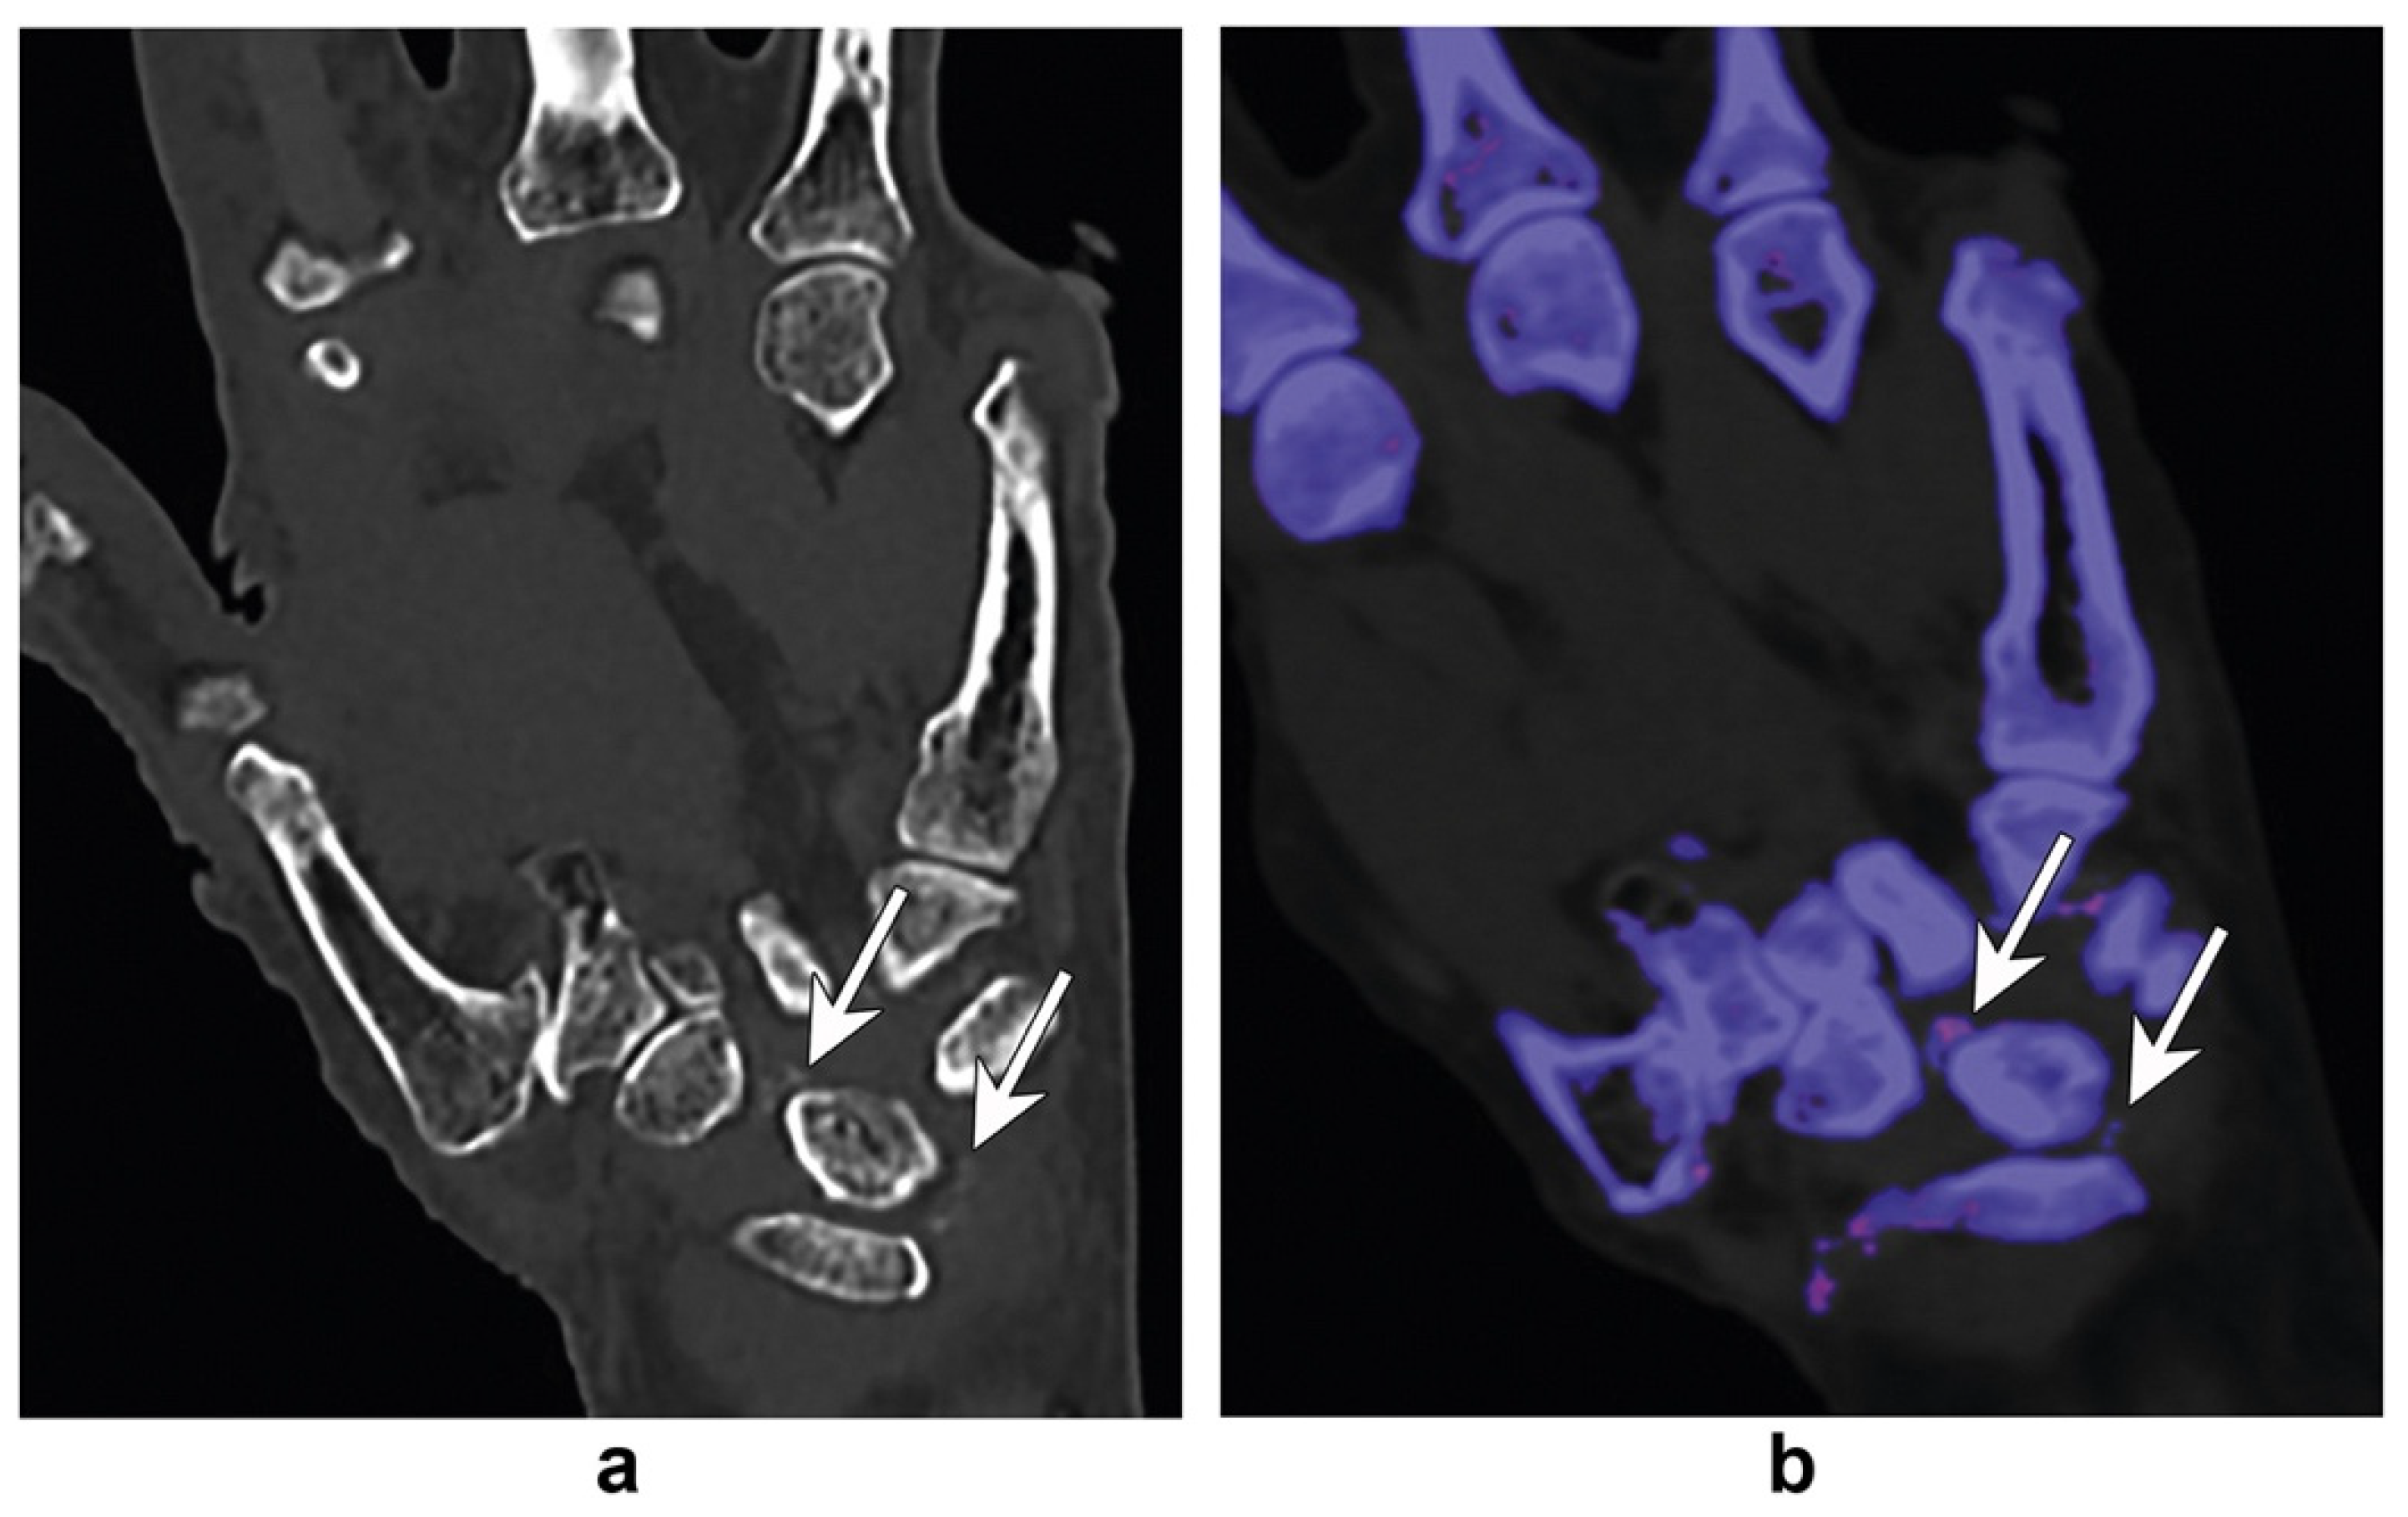

- Ali, I.T.; Wong, W.D.; Liang, T.; Khosa, F.; Mian, M.; Jalal, S.; Nicolaou, S. Clinical Utility of Dual-Energy CT Analysis of Bone Marrow Edema in Acute Wrist Fractures. AJR. Am. J. Roentgenol. 2018, 210, 842–847. [Google Scholar] [CrossRef] [PubMed]